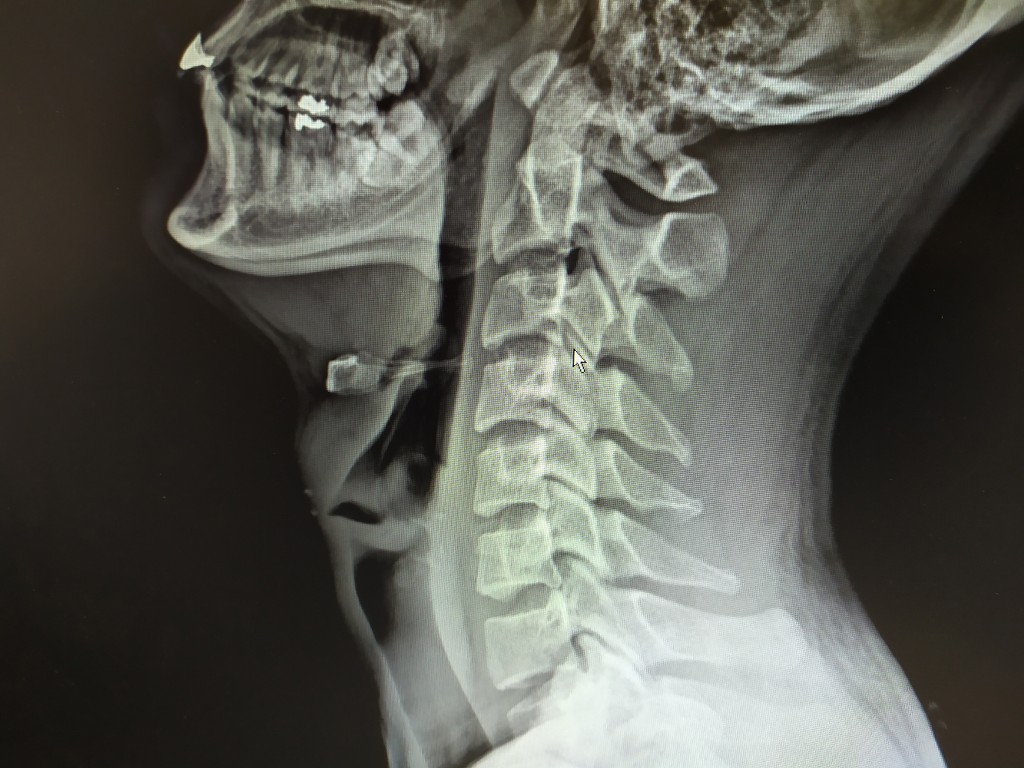

일자목이라고 해서 내가 비교를 해 달라고 하니 아래와 같이 비교를 해주더군요.

좌측이 현재 일자목이라고 판단받은 제 사진이고 우측이 2개월 정도 도수치료 받아 C자형이 되어 가고 있는 분 사진이라고 하네요.

저도 치료 받아 일자목을 C자형태로 만들어 준다고 합니다. ^^ 그러면서 어깨 통증은 염증이 있는데 도수치료로 함께 치료 가능하다고 합니다.